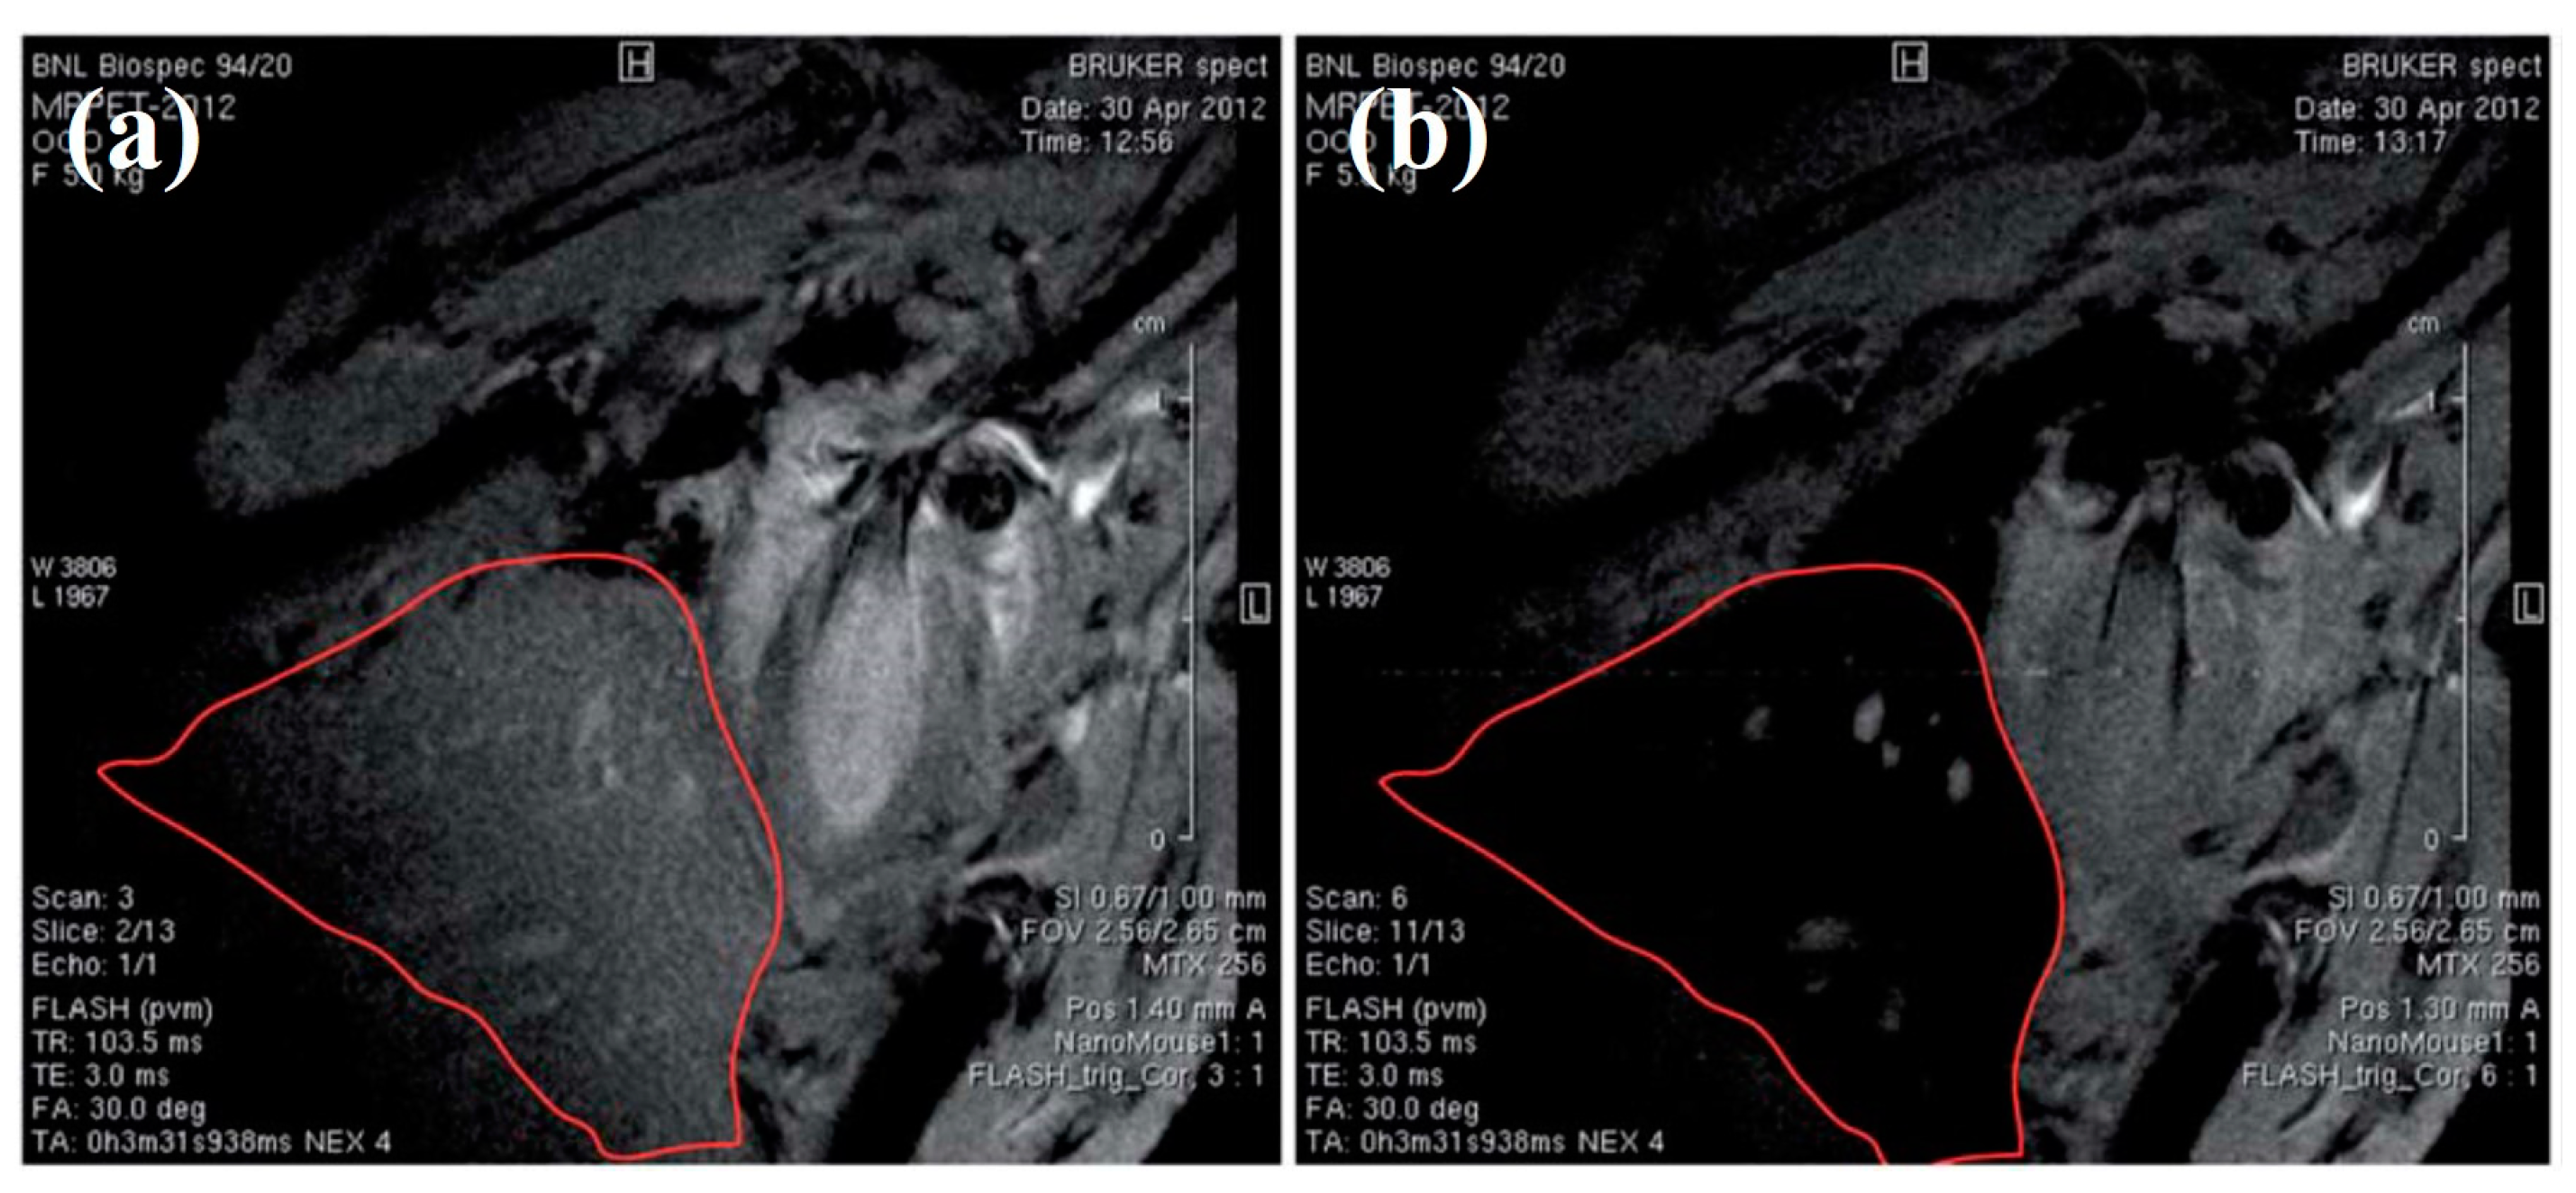

- Sharma, R.; Xu, Y.; Kim, S.W.; Schueller, M.J.; Alexoff, D.; Smith, S.D.; Wang, W.; Schlyer, D. Carbon-11 radiolabeling of iron-oxide nanoparticles for dual-modality PET/MR imaging. Nanoscale 2013, 5, 7476–7483. [Google Scholar] [CrossRef]